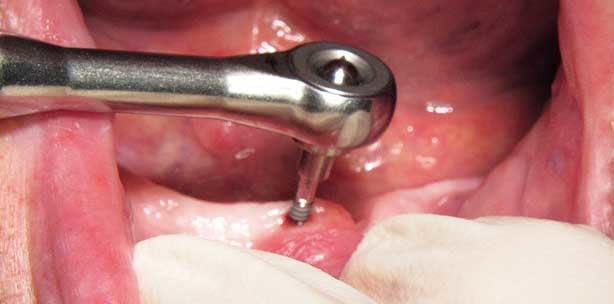

Die Insertion von vier Implantaten mit 1,8 mm Durchmesser erfolgte nach dem vorgegebenen Protokoll. Für die Eintrittsbohrung wurde ein Pilotbohrer mit einem Durchmesser von 1,1 mm gewählt, der damit schmaler als das Implantat ist (Abb. 2). Die Bohrung erfolgte ohne Lappenbildung durch die Schleimhaut und die Bohrtiefe betrug lediglich die Hälfte der Implantatlänge. Letzteres ist von Bedeutung, um die selbstschneidende Funktion des Implantates auszunutzen,die zu einer Kompression und Kondensation des Knochens führt. Hierdurch wird eine hohe Primärstabilität sichergestellt, die eine Sofortbelastung des Implantates in den meisten Fällen gewährleistet. Nach der Pilotbohrung wurde das Implantat aus der sterilen Packung entnommen und von Hand – unter leichtem Druck und im Uhrzeigersinn – mit der Verschlusskappe in den Knochen eingeschraubt (Abb. 3). Anschließend wurde die Verschlusskappe entfernt (Abb. 4) und durch einen Initialschraubendreher ersetzt, mit dem das weitere Eindrehen des Implantates möglich war (Abb. 5 und 6). Fortgesetzt wurde die Insertion mit einem Flügelschraubendreher (Abb. 7 und 8). Die Verwendung aller Instrumente erfolgte bis zum Auftreten eines leichten Widerstandes bei der Insertion. Zum Abschluss wurde das Implantat mit einer Drehmomentratsche (Abb. 9) bis zur endgültigen Position in den Knochen eingedreht (Abb. 10). Ab einem Drehmoment von 35 Ncm hat das Implantat eine ausreichende Primärstabilität erreicht. Übersteigt das Drehmoment den Schwellenwert von 45 Ncm, obwohl das Implantat noch nicht in die gewünschte Position gebracht wurde, so muss dieses herausgedreht und die Pilotbohrung erweitert werden. Insgesamt sollte das Eindrehen des Implantats möglichst langsam erfolgen, um Wärmebildung und somit eine thermische Schädigung des Knochens zu vermeiden. Die drei weiteren MDI-Implantate wurden in der gleichen Vorgehensweise inseriert. Abbildung 11 zeigt die vier Implantate in ihrer endgültigen Position.